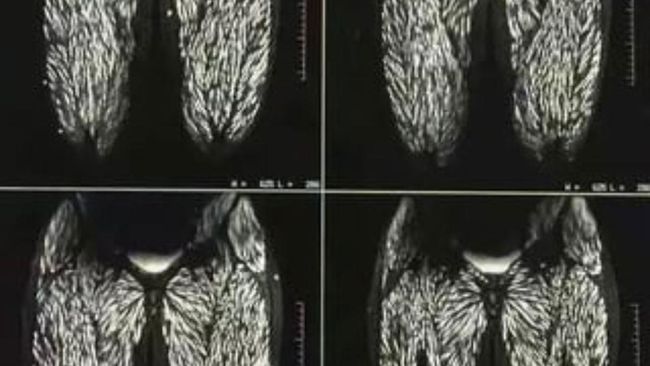

Rontgen Tubuh Wanita Penuh Parasit Akibat Sering Makan Babi Mentah. (Foto: X @PicturesFoIder)

Dikutip dari detikFood, belakangan ini ramai di media sosial kolase foto rontgen tubuh manusia yang dipenuhi parasit. Foto tersebut viral setelah diunggah oleh akun X @PicturesFoIder (22/08/24).

Dalam klaimnya, tubuh wanita itu mengalami infeksi parasit akibat sering makan daging babi mentah selama 10 tahun. Unggahannya viral hingga di mendapat view 38.2 juta.

Serangkaian gambar medis tersebut tersebar di berbagai platform media sosial pada Agustus 2024. Konon, itu merupakan tubuh seorang wanita berusia 23 tahun asal China.

Dikutip dari Snopes (12/09/24) ada informasi yang benar dan ada pula yang salah pada berita tersebut. Memang fakta bahwa rontgen itu memperlihatkan bagian tubuh seorang wanita.

Itu merupakan rontgen tubuh bagian bawah dan kaki yang benar terinfeksi parasit akibat seringnya makan daging babi mentah. Foto rontgen itu diambil ketika si wanita masih berusia 23 tahun.

Saat itu, dilaporkan bahwa wanita tersebut memang selalu makan daging babi mentah sejak usia 10 tahun.